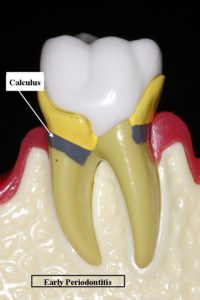

A destructive infection of the gum and underlying bone. It is gingivitis that has gotten out of control and has started to destroy the connection between the gum and the tooth. It is characterized by red, swollen and bleeding gums and will result in tooth loss if it is not treated. The infection causes the bone and ligament which hold the tooth in place to be destroyed. It is also known as periodontal disease and Pyorrhea. How aggressively the infection destroys the bone and gum which support the teeth is influenced by whether or not the patient smokes, if they are diabetic, if they are genetically predisposed, if they are on certain medications and if they clench and grind their teeth. Gum infection has also been linked to cardiovascular disease, stroke, low birth weight and preterm newborns, difficulty in controlling diabetes and recent evidence suggests it may affect Alzheimer’s and upper respiratory tract infections.